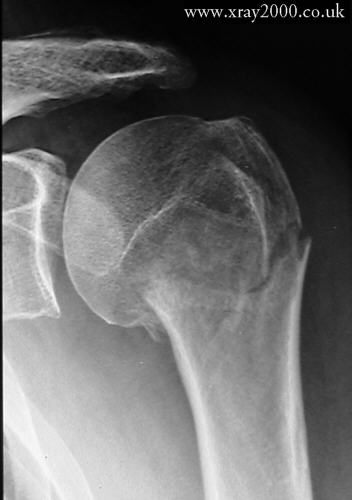

Какой синдром патологии костной ткани вы видите на данной рентгенограмме// Остеомаляция// Остеопороз// +Остеосклероз// Гипреостоз// Остеолизис

Какой синдром патологии костной ткани вы видите на данной рентгенограмме// Остеомаляция// Остеопороз// Остеосклероз// Гипреостоз// +Остеолизис

Какой синдром патологии костной ткани вы видите на данной рентгенограмме// Остеомаляция// Остеопороз// Остеосклероз// +Гипреостоз// Остеолизис

Какой синдром патологии костной ткани вы видите на данной рентгенограмме// +Остеомаляция// Остеопороз // Остеосклероз// Гипреостоз// Остеолизис

Какой синдром патологии костной ткани вы видите на данной рентгенограмме // Остеомаляция// Остеопороз// +Остеосклероз// Гипреостоз// Остеолизис